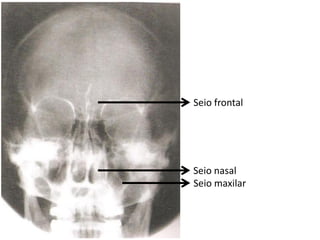

Radiografia do crânio

• Estruturas internas são mais estudadas com aquisições de

imagens mais detalhadas.

Alterações visualizadas:

Fraturas;

Neoplasias;

Inflamações;

Distúrbios articulares (ATM);

Lesões por PAF;

Adenomas hipofisários;

Mieloma múltiplo;

Doença de Paget (osteíte deformante).

Seio frontal

Seio nasal

Seio maxilar